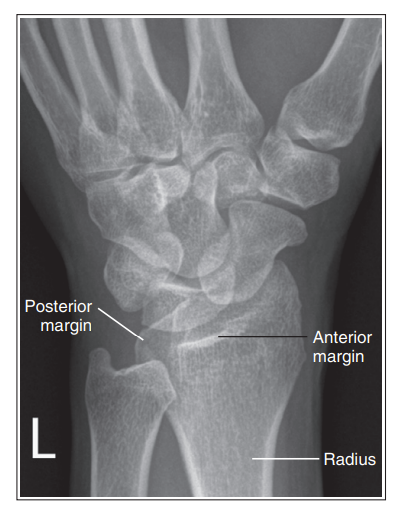

Anterior tibial margin is lateral to posterior margin

External rotation

Posterior tibial margin is lateral to anterior and is superimposed by talus

Internal rotation